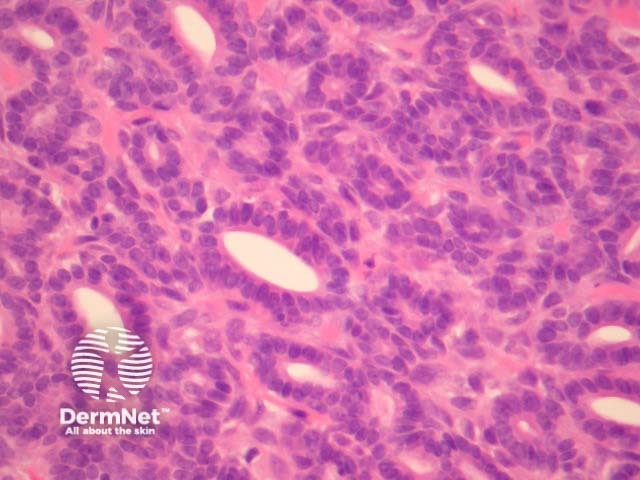

Polymorphous sweat gland carcinomas are dermally based tumours (figure 1) that show a wide range of morphologic growth patterns ranging from solid, tubular (figures 2, 3), cribriform (figure 4) and ductal. Abrupt transitions between morphologies is a characteristic feature (figure 5, 6).

Figure 2

Figure 3